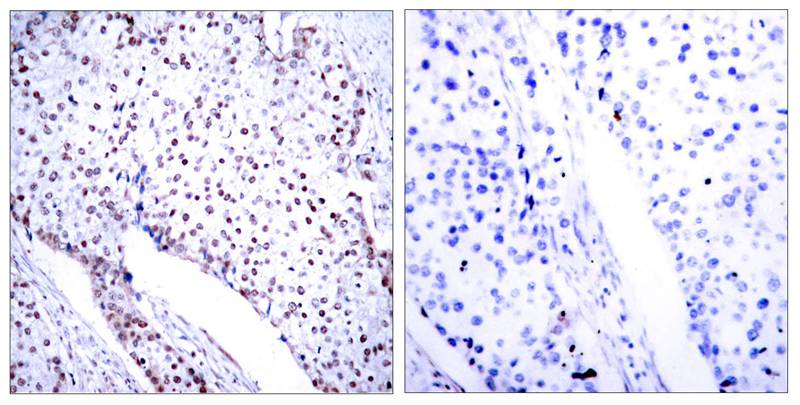

分类: 科研抗体货号: P41247别名: NFKB3; RELA; TF65; Transcription factor p65; p65应用: WB,IHC,IF反应种属: Human,Mouse,Rat